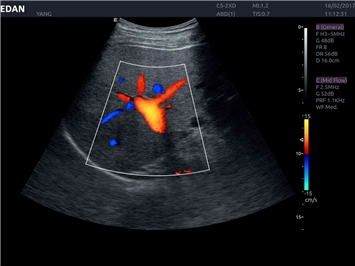

• Кардиологических исследований

Трехмерная реконструкция ЦДК:

Да